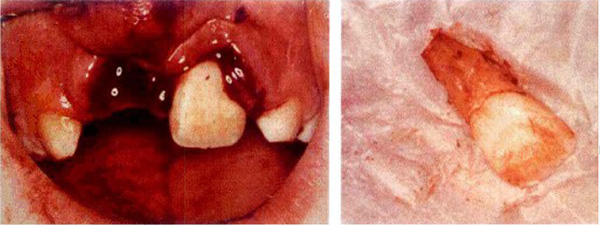

牙齿脱落后,错误的将牙齿包裹在纸中

牙齿脱落后污染,要尽量只触碰图中白色的牙冠部分

一些家长将脱落的牙齿找到后,发现牙面上有许多泥土和血渍,会特意用刷子将牙面刷的干干净净,并用含酒精的消毒纸巾包裹着来就医,这些错误的做法将直接导致患牙再植成功率大大降低。